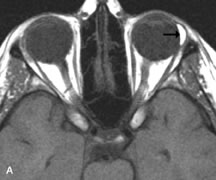

Tl relaxation time is the time required for the energized nuclei to give up the excess energy that was acquired from the RF pulse (high-energy state) and re-establish equilibrium (low-energy state) with the main magnetic field. The excess energy is released by these excited nuclei to the surrounding molecular environment, or lattice, and results in T1 relaxation, also called spin-lattice relaxation time. In different biologic tissues, hydrogen has a Tl ranging from a few hundred milliseconds to a couple of seconds. This range exists because local tissue factors affect the ability of specific protons to give up energy to the surrounding tissues. For example, hydrogen atoms attached to the carbon atoms of fat molecules relax much more rapidly than those attached to the oxygen atoms of water molecules. Viscosity, concentration, temperature, and molecular environment of the hydrogen atoms in the tissues also affect the T1 relaxation time. On a T1-weighted orbital image, fat, which has a very short T1 relaxation time, yields a high-intensity signal; the rectus muscles, which have an intermediate T1, yield an intermediate-intensity signal; and the vitreous, which has a long T1, yields a low-intensity signal (Fig. 8).5,8,16